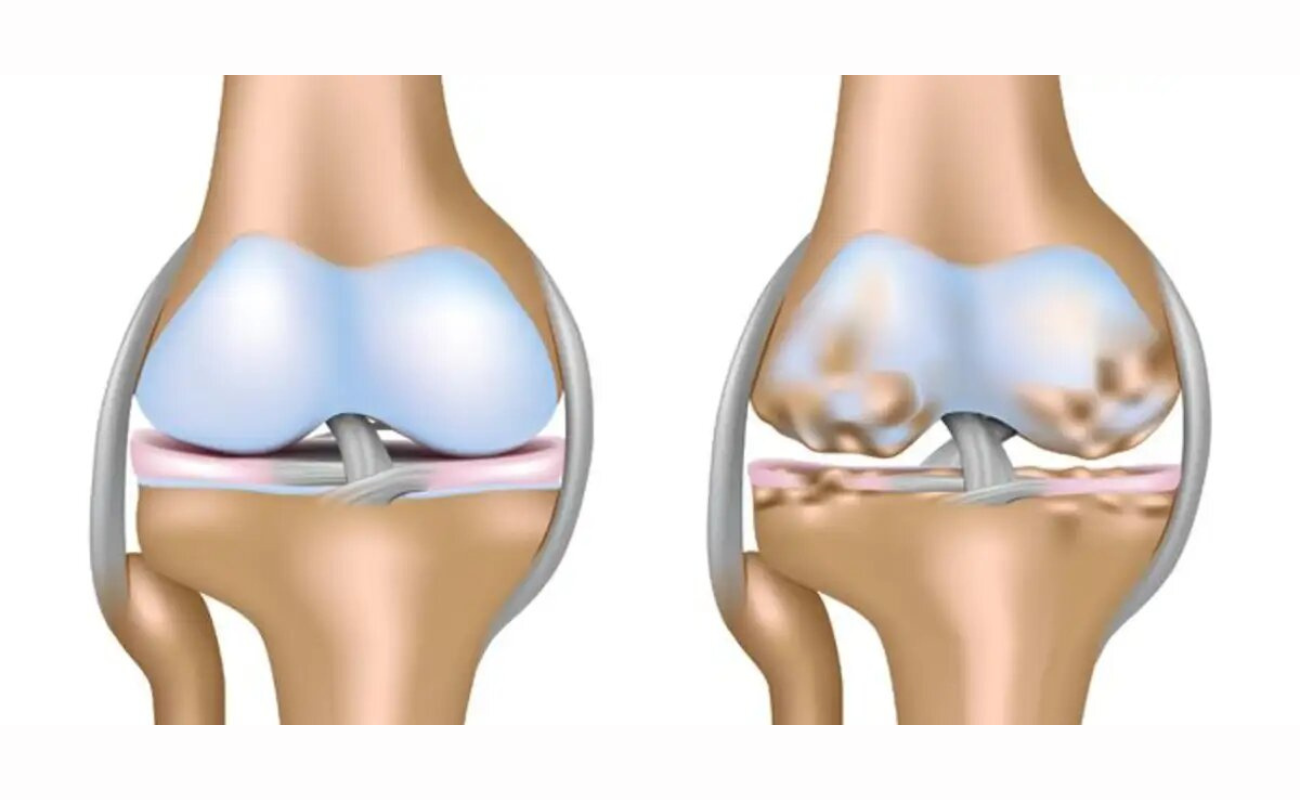

Osteoarthritis

Osteoarthritis leads to loss of cartilage when rate of cartilage damage exceeds the rate of repair. Cartilage is necessary to prevent bones from rubbing against each other. When the cartilage cover is lost, the bones come into contact and result in painful movement.

Articular Cartilage Damage

Articular Cartilage is the layer of smooth connective tissue that covers the ends of bones at every joint. This tissue is maintained and repaired on a continuous basis. It is one of the most lubricated materials on earth and has the lowest coefficient of friction,

Managing Knee Osteoarthritis: Non-Surgical Options to Consider

Knee osteoarthritis is a common condition characterized by the gradual deterioration of cartilage in the knee joint. It can cause pain, stiffness, swelling, and reduced mobility,